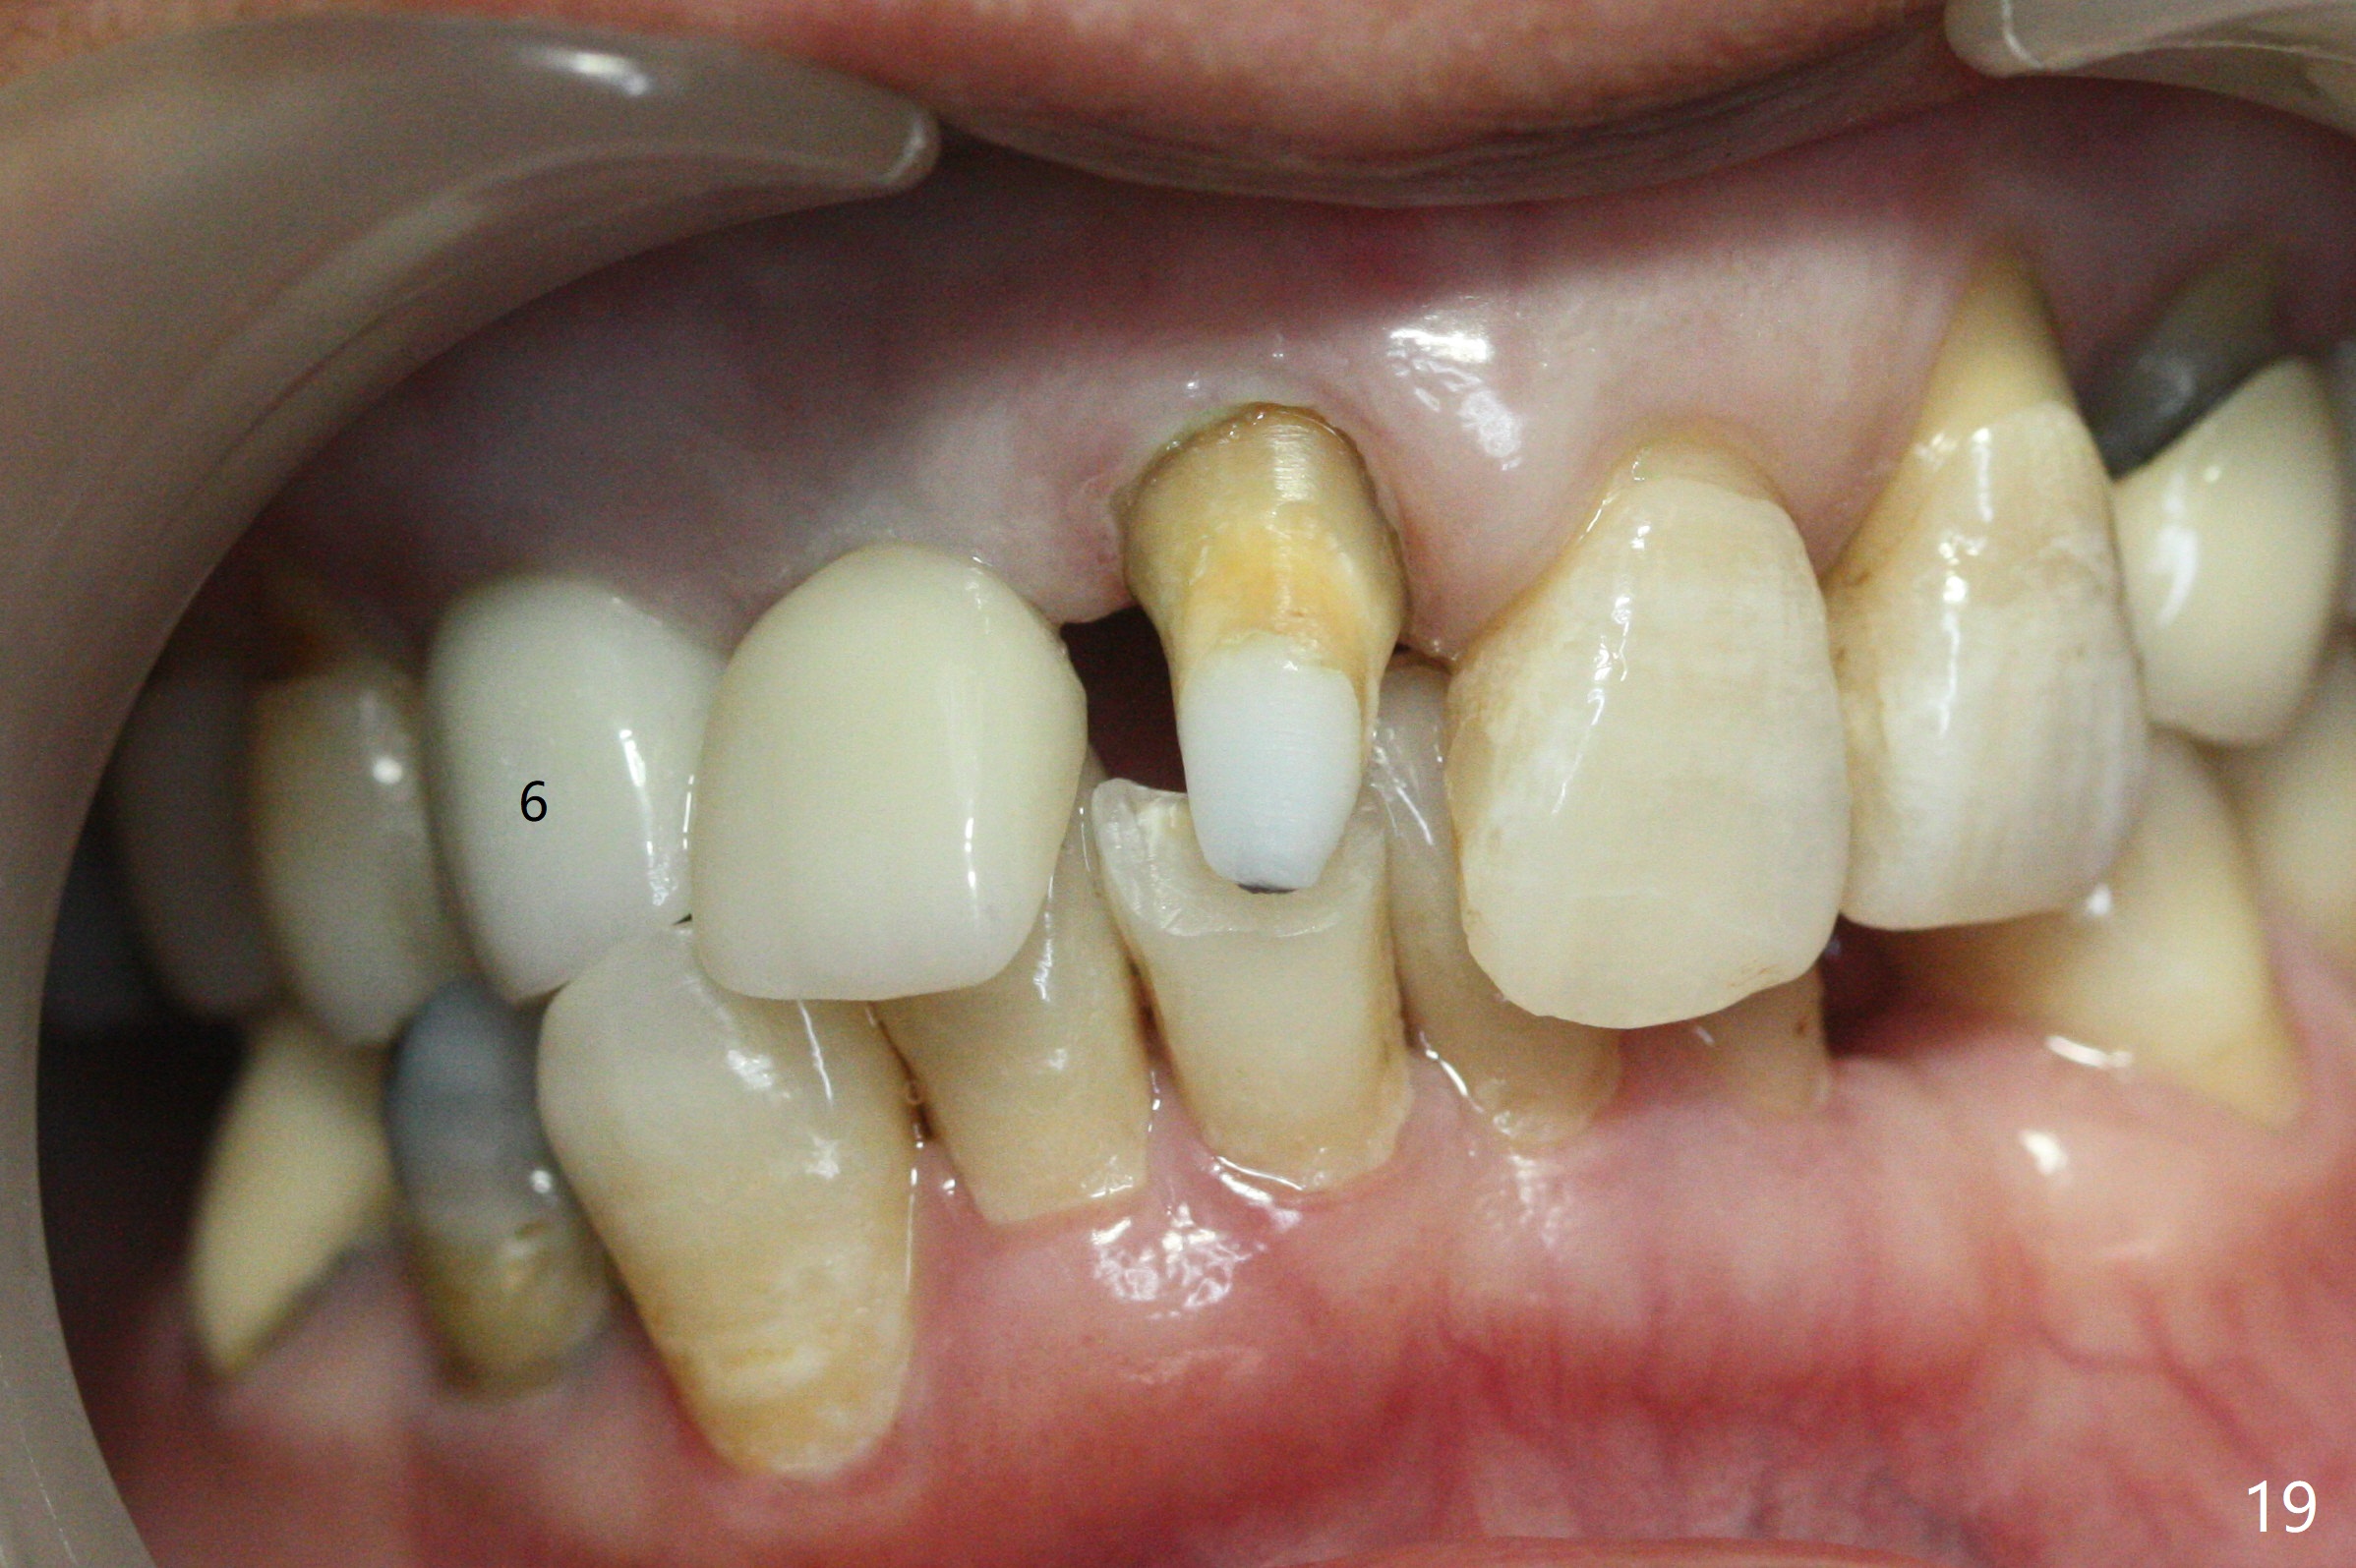

When the bridge is sectioned between #7 and 8, the tooth #6 is found non-salvageable (Fig.1).  Incision shows the atrophic buccal plate at #7 (Fig.2 arrowheads); to prevent the same feature from happening at #6 with thin buccal plate, the most buccal portion of the root is preserved (socket shield (Fig.2-4: *)).  The initial osteotomy is established in the palatal slope at #6 (Fig.5 circle) with 1.5 mm drill (Fig.6,7).  A portion of the root is visible in Fig.6 (arrowheads).  After sequential osteotomy with 2 mm, 3 mm (Fig.8) and 3.2 mm drills, a 4x15 mm implant is placed (Fig.10).  To accommodate the cross bite, the coronal portion of the implant (Fig.9 white circle) is positioned close to the socket shield.  It appears that the shield prevents the implant from encroaching the buccal plate.

Since the ridge at #7 is ~ 4 mm, a 2.5x14 mm 1-piece implant is placed (Fig.8) after 1.2 mm (Fig.7), and 1.5 mm drills at 12 mm and 2 mm drill at 8 mm.  Later the implant is placed deeper (Fig.10).  There is no bone loss 7 or 12 months postop, respectively (Fig.11,12).  After Diode gingivectomy, there is papillary formation (Fig.13).  No provisional is provided after impression (with the abutment torqued at #6) for oral hygiene.  With access holes at #6 and 7, crowns are bonded with minimal residual cement (Fig.14 <, which is removed later).  There is no hard (Fig.15,16) or soft (Fig.17 *) atrophy 26 months postop, i.e., 13 months post cementation, due to the presence of socket shield (Fig.15 <, as compared to Fig.1).  In fact the tooth #8 has mobility and fremitus (short root/poor crown/root ratio, Fig.16); occlusal adjustment is done 13 months post cementation.  The crown is dislodged 2 years 1 month post cementation; a prefabricated post is being tried in (Fig.18).  There is no atrophy, bone loss or infection at #6 (with socket sheath (*)) or 7 two years 5 months post cementation (Fig.20-27).